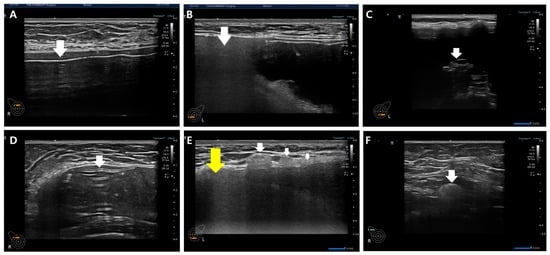

For the diagnosis of silicone breast implant (SBI) rupture, the presence of free silicone, characterized by spontaneous hypo-echogenicity in ultrasonography, or the identification of a shell tear manifesting as a disrupted thin linear hyper-echogenicity or gel fracture sign, was considered (Figure 7).

Gel bleeding is indicative of free silicone without shell tears. SBI rupture is characterized by a gel fracture and stepladder sign in implant integrity, as illustrated in Figure 7C and D. In some cases, rupture diagnosis may solely rely on the presence of gel fracture without the simultaneous occurrence of free silicone and shell tear in ultrasonography (Figure 7C). Upon confirming rupture, the evaluation and documentation of snowstorm signs and the extent of silicone migration to adjacent tissue or regional lymph nodes are performed (Figure 7E,F). This record is crucial information for physicians and patients, helping prevent unnecessary biopsies prompted by remnant silicone migration to adjacent tissues and regional lymph nodes.

3.4.2. Current Classification of Silicone Breast Implant Rupture Scope

The existing silicone breast implant rupture classification distinguishes between intracapsular and extracapsular ruptures based on imaging diagnoses using mammography (MMG), ultrasound, or MRI. In the current framework, intracapsular ruptures are characterized by the absence of silicone migration to adjacent tissue in MMG, ultrasound, or MRI images. In contrast, extracapsular ruptures are identified by a snowstorm appearance in ultrasonography (Figure 7B,E) and the migration of silicone to adjacent tissue or regional lymph nodes, detectable by MMG and MRI. The classification by MMG and MRI into intra- and extracapsular ruptures stems from their inability to display posterior acoustic shadowing. In contrast, ultrasonography, with its ability to reveal posterior acoustic shadowing (snowstorm signs) and detect silicone migration to adjacent tissue or regional lymph nodes, introduces a more nuanced approach by dividing silicone breast implant ruptures into three types.

Figure 7. Various diagnostic clues in silicone breast implant rupture. (A) Free silicone (indicated by a white arrow), (B) snowstorm sign (indicated by a white arrow), (C) gel fracture sign (indicated by a white arrow), (D) stepladder sign (indicated by a white arrow), (E) adjacent silicone migration (indicated by a white arrow) with snowstorm sign (indicated by a yellow arrow), and (F) silicone migration to regional lymph nodes (indicated by a white arrow).